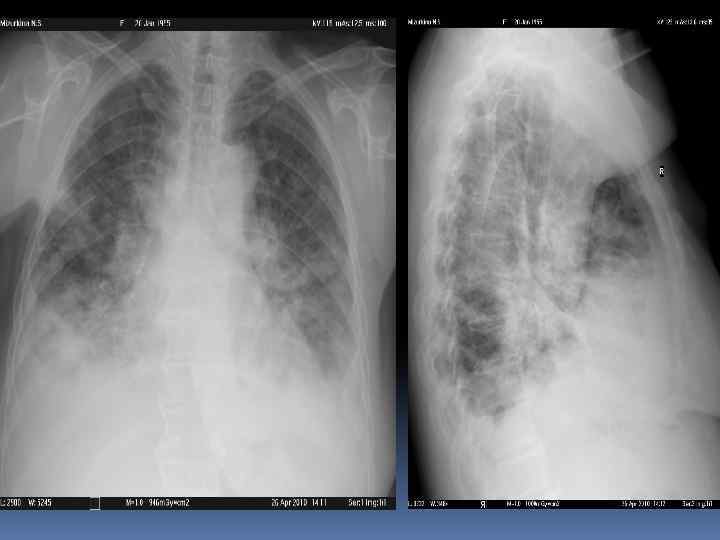

Изменение гемодинамики малого круга – ЛВГ, ЛАГ, интерстициальный отек

Изменение гемодинамики малого круга – ЛВГ